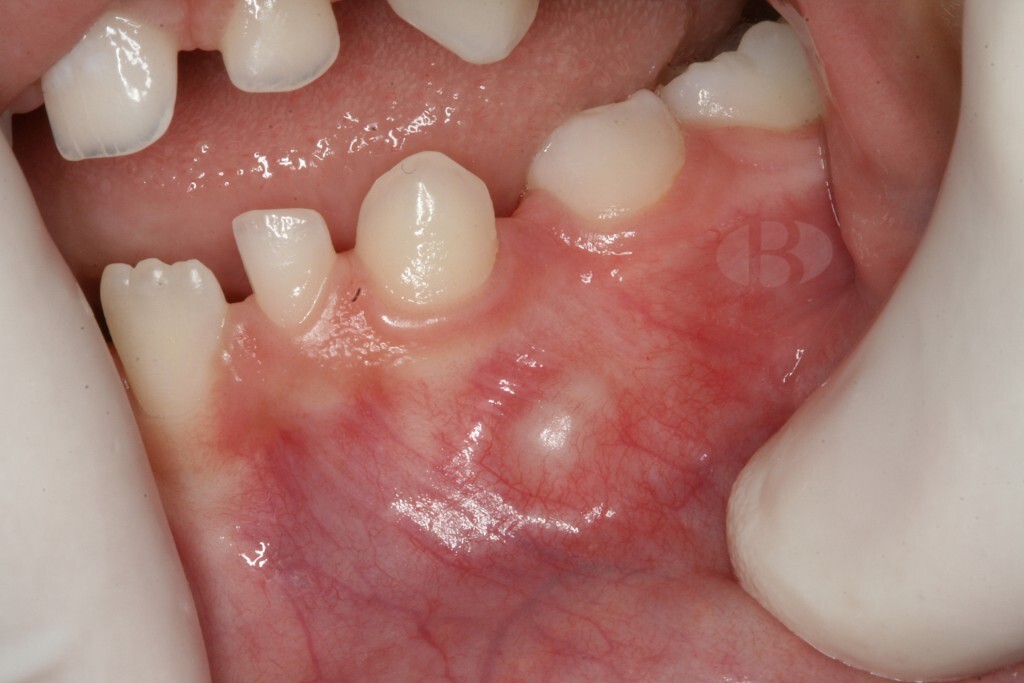

Silent Killers: Understanding How Gingivitis and Periodontitis Can Gradually Destroy Your Teeth

Have you ever experienced the sharp, throbbing pain of a toothache that just won’t quit? Or perhaps, you’ve felt a dull ache in your gums that persists even after brushing and flossing diligently? If so, you may be one of the millions of people worldwide who suffer from periodontitis, a common and often overlooked condition that can lead to serious dental problems if left untreated. Specifically, periodontal disease represents a slow and insidious death for the teeth, gradually “melting” away the bone tissue that holds the teeth firmly in place.

Periodontitis, specifically, is a pervasive oral health issue that affects millions of people worldwide, ranging from mild forms that can be treated easily to more severe cases that can result in tooth loss and require extensive medical intervention. Statistics show that severe periodontal disease affects 19% of the global population (1 billion people).  This makes it the sixth most common disease worldwide.

Phase 1: Gingivitis

Periodontitis and its precursor, gingivitis often go unnoticed until significant damage has already been done and in many cases – irreversible. Gingivitis is essentially inflammation of the gums, which in its turn is an effect of plaque buildup from inadequate oral hygiene. The bacteria in plaque produce toxins that can damage the gums and cause them to pull away from the teeth, forming pockets where more bacteria can accumulate. This vicious cycle leads to deepening of the pockets, and the gums starting to recede, exposing the roots of the teeth. This can cause sensitivity, pain, and eventually, tooth loss.

Risks of leaving gingivitis untreated

Gum disease often goes undetected and, when untreated, can cause irreversible damage to soft tissue and bone. This leads to gum recession, jawbone deterioration and eventually to tooth loss.

Progression to periodontitis

Periodontitis is a complex and mystifying process where certain types of bacteria cause damage to the gum tissue and bone structure supporting our teeth. As discussed it is usually preceded by gingivitis – the mild form of gum disease, that can progress to a more severe and damaging form.

Periodontitis begins with the accumulation of dental plaque, a biofilm composed of bacteria and extracellular matrix, on the teeth and gums. The bacteria in the plaque trigger the host’s immune response, leading to inflammation of the gingival tissue. The initial inflammatory response is characterized by increased blood flow and vascular permeability, which allows immune cells and proteins to infiltrate the affected tissue. In some individuals, the inflammatory response is not effectively resolved, resulting in persistent inflammation and destruction of the connective tissue and alveolar bone that support the teeth.

Early signs are often subtle, including bleeding gums, persistent bad breath, and slight discomfort while chewing. Without treatment, these symptoms worsen and more complications add up. Thus in the later stages of the disease, a person experiences bleeding and receding gums, deep pockets between the teeth and gums, loose teeth, changes in bite or tooth alignment, pus around the teeth and gums.

Though this article and the pictures in it may indeed look shocking, there is no room for panic. Remember that both gingivitis and periodontitis are diseases that take many years to develop, thus there’s a lot we can do about it.